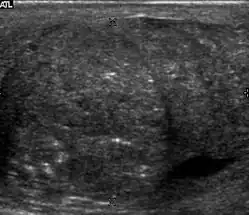

Patients with testicular lymphoma are usually old aged around 60 years of age, present with painless testicular enlargement and less commonly with other systemic symptoms such as weight loss, anorexia, fever and weakness. Bilateral testicle involvements are common and occur in 8.5% to 18% of cases. At sonography, most lymphomas are homogeneous and diffusely replace the testis [Fig. 7]. However focal hypoechoic lesions can occur, hemorrhage and necrosis are rare. At times, the sonographic appearance of lymphoma is indistinguishable from that of the germ cell tumors [Fig. 8], then the patient's age at presentation, symptoms, and medical history, as well as multiplicity and bilaterality of the lesions, are all important factors in making the appropriate diagnosis.

Primary leukemia of the testis is rare. However, due to the presence of blood-testis barrier, chemotherapeutic agents are unable to reach the testis, hence in boys with acute lymphoblastic leukemia, testicular involvement is reported in 5% to 10% of patients, with the majority found during clinical remission. The sonographic appearance of leukemia of the testis can be quite varied, as the tumors may be unilateral or bilateral, diffuse or focal, hypoechoic or hyperechoic. These findings are usually indistinguishable from that of the lymphoma [Fig. 9].